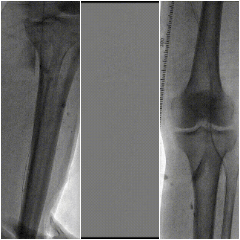

图:术中CT

3

手术结果

图:术后效果